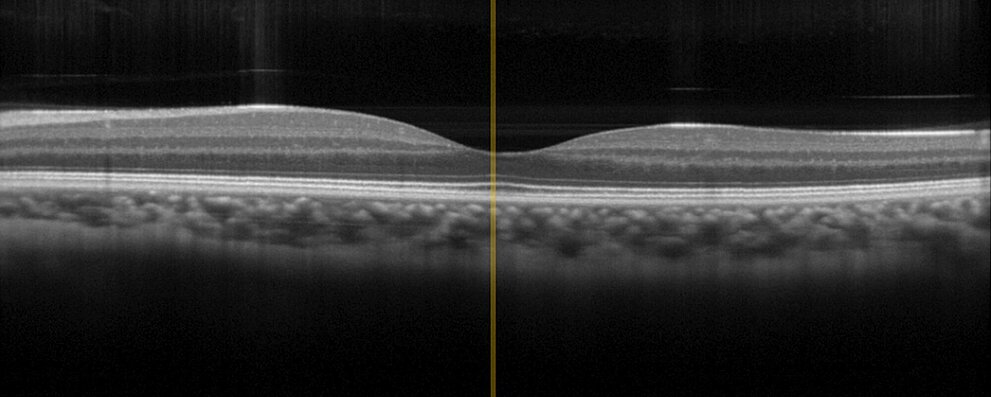

内視鏡検査および生体内診断は、生体内または生体に適用されるため、最も精巧な医療技術のひとつです。ここでは最も高い信頼性が不可欠です。PIの数十年におよぶ医療技術企業へのサプライヤとしての経験と、ピエゾコンポーネントの製造者としての30年間の経験は、PIがアセンブリとサブシステムの開発と製造に貢献する重要な財産です。例えば、PIは、チップオンザチップ内視鏡の可変焦点化のために、1つだけではなく、複数のドライブを提供しています。また、眼科学や皮膚病学における光干渉断層計 (OCT) のために、PIは、光学系の正確な位置決めのために、サイズや移動範囲などの装置固有の要件に適合することができる様々な駆動技術を提供します。